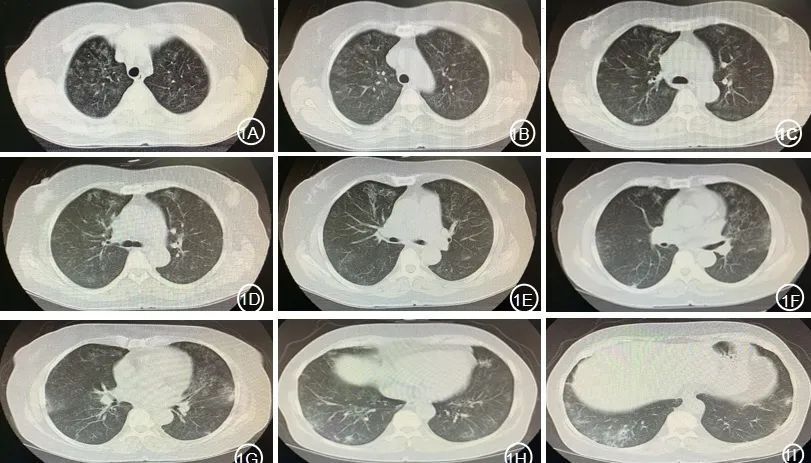

双肺广泛小叶间隔增厚